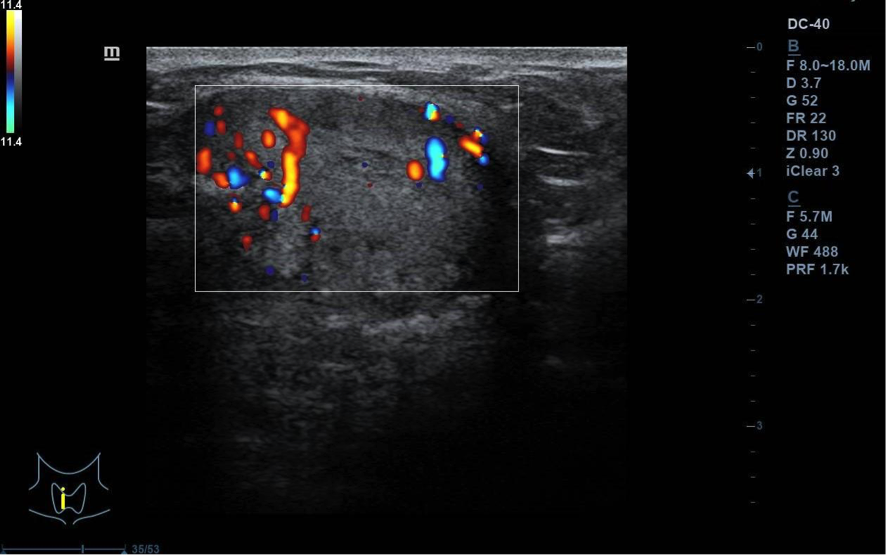

Se visualiza nódulo tiroideo en la unión del istmo con lóbulo tiroideo derecho, sólido, con cierta heterogenicidad, halo grueso anecogénico. Una zona del borde irregular, con mayor señal Doppler y de crecimiento excéntrico. Mide de diámetro máximo 25 x 20 mm. Adenopatías no patológicas.